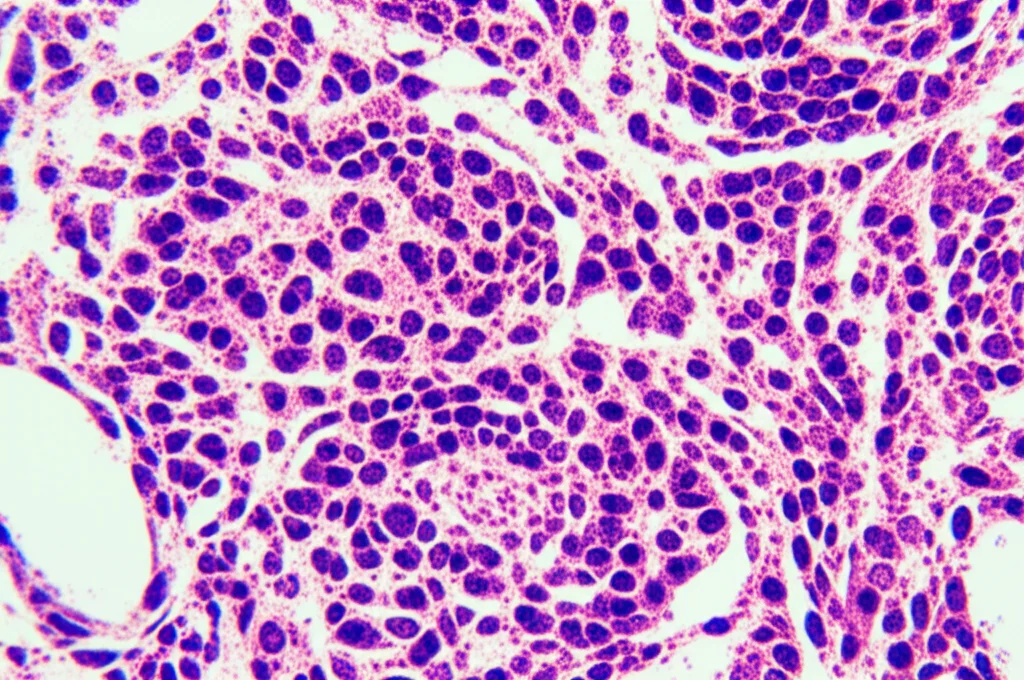

Quando parliamo di linfoma in questi casi, il protagonista più frequente è il linfoma non-Hodgkin (NHL), che rappresenta la totalità dei 35 casi analizzati. E all’interno degli NHL, la forma più comune è il linfoma diffuso a grandi cellule B (DLBCL), riscontrato nel 40% dei pazienti. Seguono poi altre forme come il linfoma linfocitico a piccole cellule/leucemia linfatica cronica (SLL/CLL) e il linfoma della zona marginale (MZL).

È interessante notare come la combinazione più comune sia stata DLBCL insieme a PTC, un dato che, seppur basato su un campione limitato, offre spunti di riflessione.